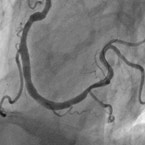

Behandelte Kranzaterie ohne Verengung